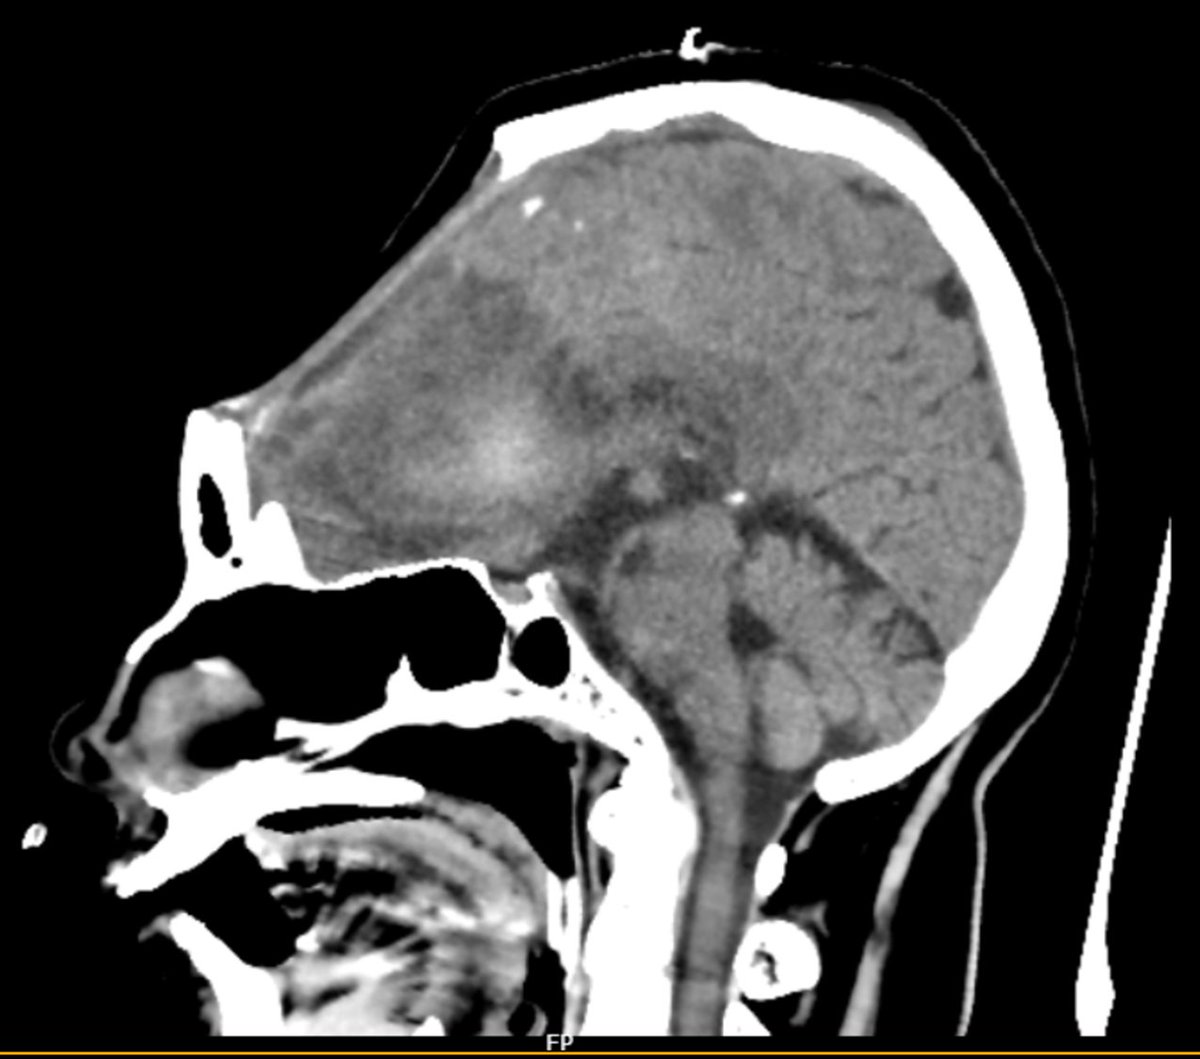

Clinical pearl; "Syndrome of the trephined" or "sinking skin flap syndrome"- an iatrogenic complication in which neurological deterioration occurs following craniectomy. Atmospheric pressure is > ICP and leads to slow brain herniation.

Read about Sunken Scalp Flap Syndrome, Sinking Skin Flap Syndrome (SSFS), or Syndrome of the Trephined at jbsr.be/articles/10.53…